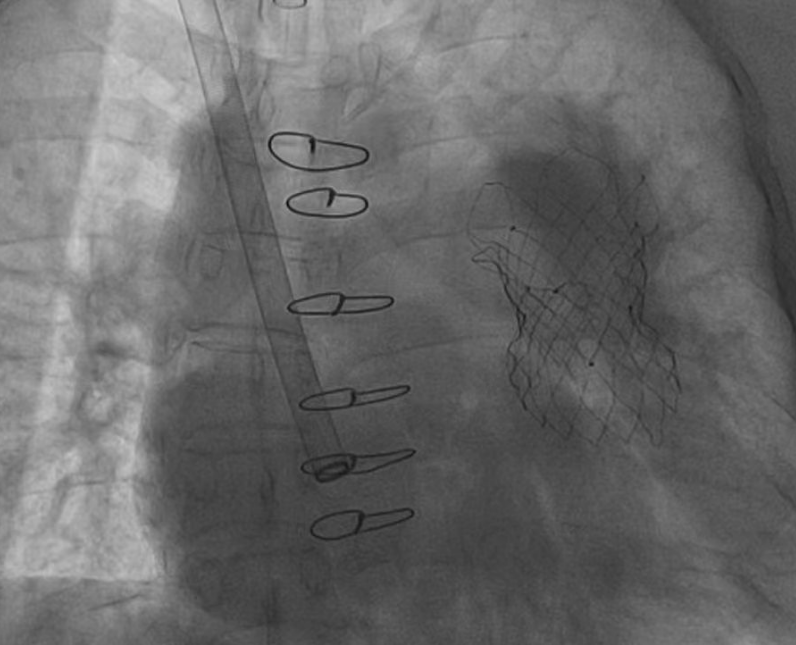

患者术后肺动脉瓣反流得到显著改善

由于患者存在下腔静脉肝段缺失,因此此次手术选择经颈静脉入路。中大医院麻醉科陆新健主治医师为患者麻醉后,马根山教授带领团队穿刺颈静脉,送入超硬导丝,经上腔静脉建立通路后送入顺应性球囊,打起球囊后进行测量,接着根据测量选择对应型号的瓣膜,沿超硬导丝送入输送器,送至肺动脉分叉处开始释放瓣膜,释放完成后位置准确,形态良好。术后超声显示几乎无瓣周漏,血流动力学稳定,瓣膜支架形态良好,肺动脉瓣反流得到显著改善,手术圆满成功。